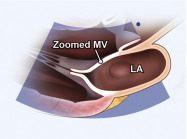

| 2.4. Mặt cắt trục dài cạnh ức phóng đại van hai lá |

||||||||

Cửa sổ siêu âm cạnh ức

Mặt cắt trục dài cạnh ức Đặt hộp phóng đại vào vị trí van hai lá Ghi được toàn bộ chuyển động của hai lá van, đoạn gần của dây chằng và vòng van. |

Van hai lá (MV)

Nhĩ trái (LA) |

|||||